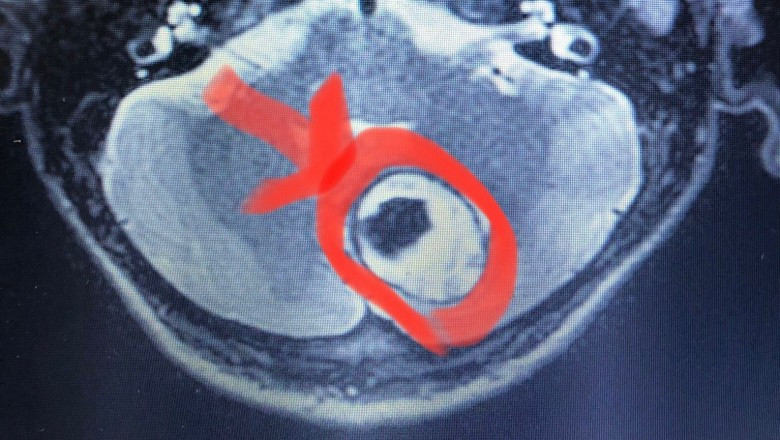

Sağlık alanında her geçen gün kendini yenileyen Yalova Devlet Hastanesi ilklere imza atmaya devam ediyor. Bu kapsamda Beyin Cerrahi Dr. Ali Rıza Özcan tarafından Nöronavigasyon-Mikro Cerrahi yöntemi ile beyincik tümörü ameliyatı gerçekleştirildi.

“ Hastanemizin Beyin Cerrahi Polikliniğine, 10 gündür baş dönmesi ve yüzde eğrilme şikayeti ile başvuran 56 yaşındaki M.S.E. adlı hastaya yapılan tetkiklerde beyinciğin sol yarısında 4 cm büyüklüğünde ve beyin sapına baskı yapan tümör tespit edildi.

Hastanemiz bünyesinde ilk defa Operatör Dr. Ali Rıza Özcan tarafından yapılan Nöronavigasyon-Mikro Cerrahi yöntemi ile tümör tamamen çıkarıldı.

Operasyon sonrası baş dönmesi ve yüzde eğrilme şikâyetinde düzelmeler tespit edildi. Ciddi hayati tehlikesi olmasına rağmen başarılı bir operasyonla sağlığına kavuşturulup şifa ile taburcu edildi.” İfadelerine yer verildi.

Ameliyat esnasında tümörün yerleşimini ve doğru giriş noktasını gösteren operasyonu kolaylaştıran, operasyonu hasta için konforlu hale getiren cerrahi bir sistemdir.